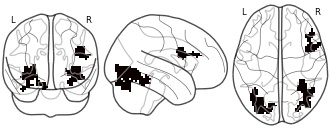

"description": "Multi-modal analysis in BPD. Brain regions exhibiting greater gray matter and enhanced activation during emotion processing in BPD compared to healthy controls. Note: Results were thresholded at p<.0025. Note2: Results were updated (see Erratum for this publication).",

"description": "Multi-modal analysis in BPD. Brain regions exhibiting smaller gray matter and enhanced activation during emotion processing in BPD compared to healthy controls. Note: Results were thresholded at p<.0025. Note2: Results were updated (see Erratum for this publication).",